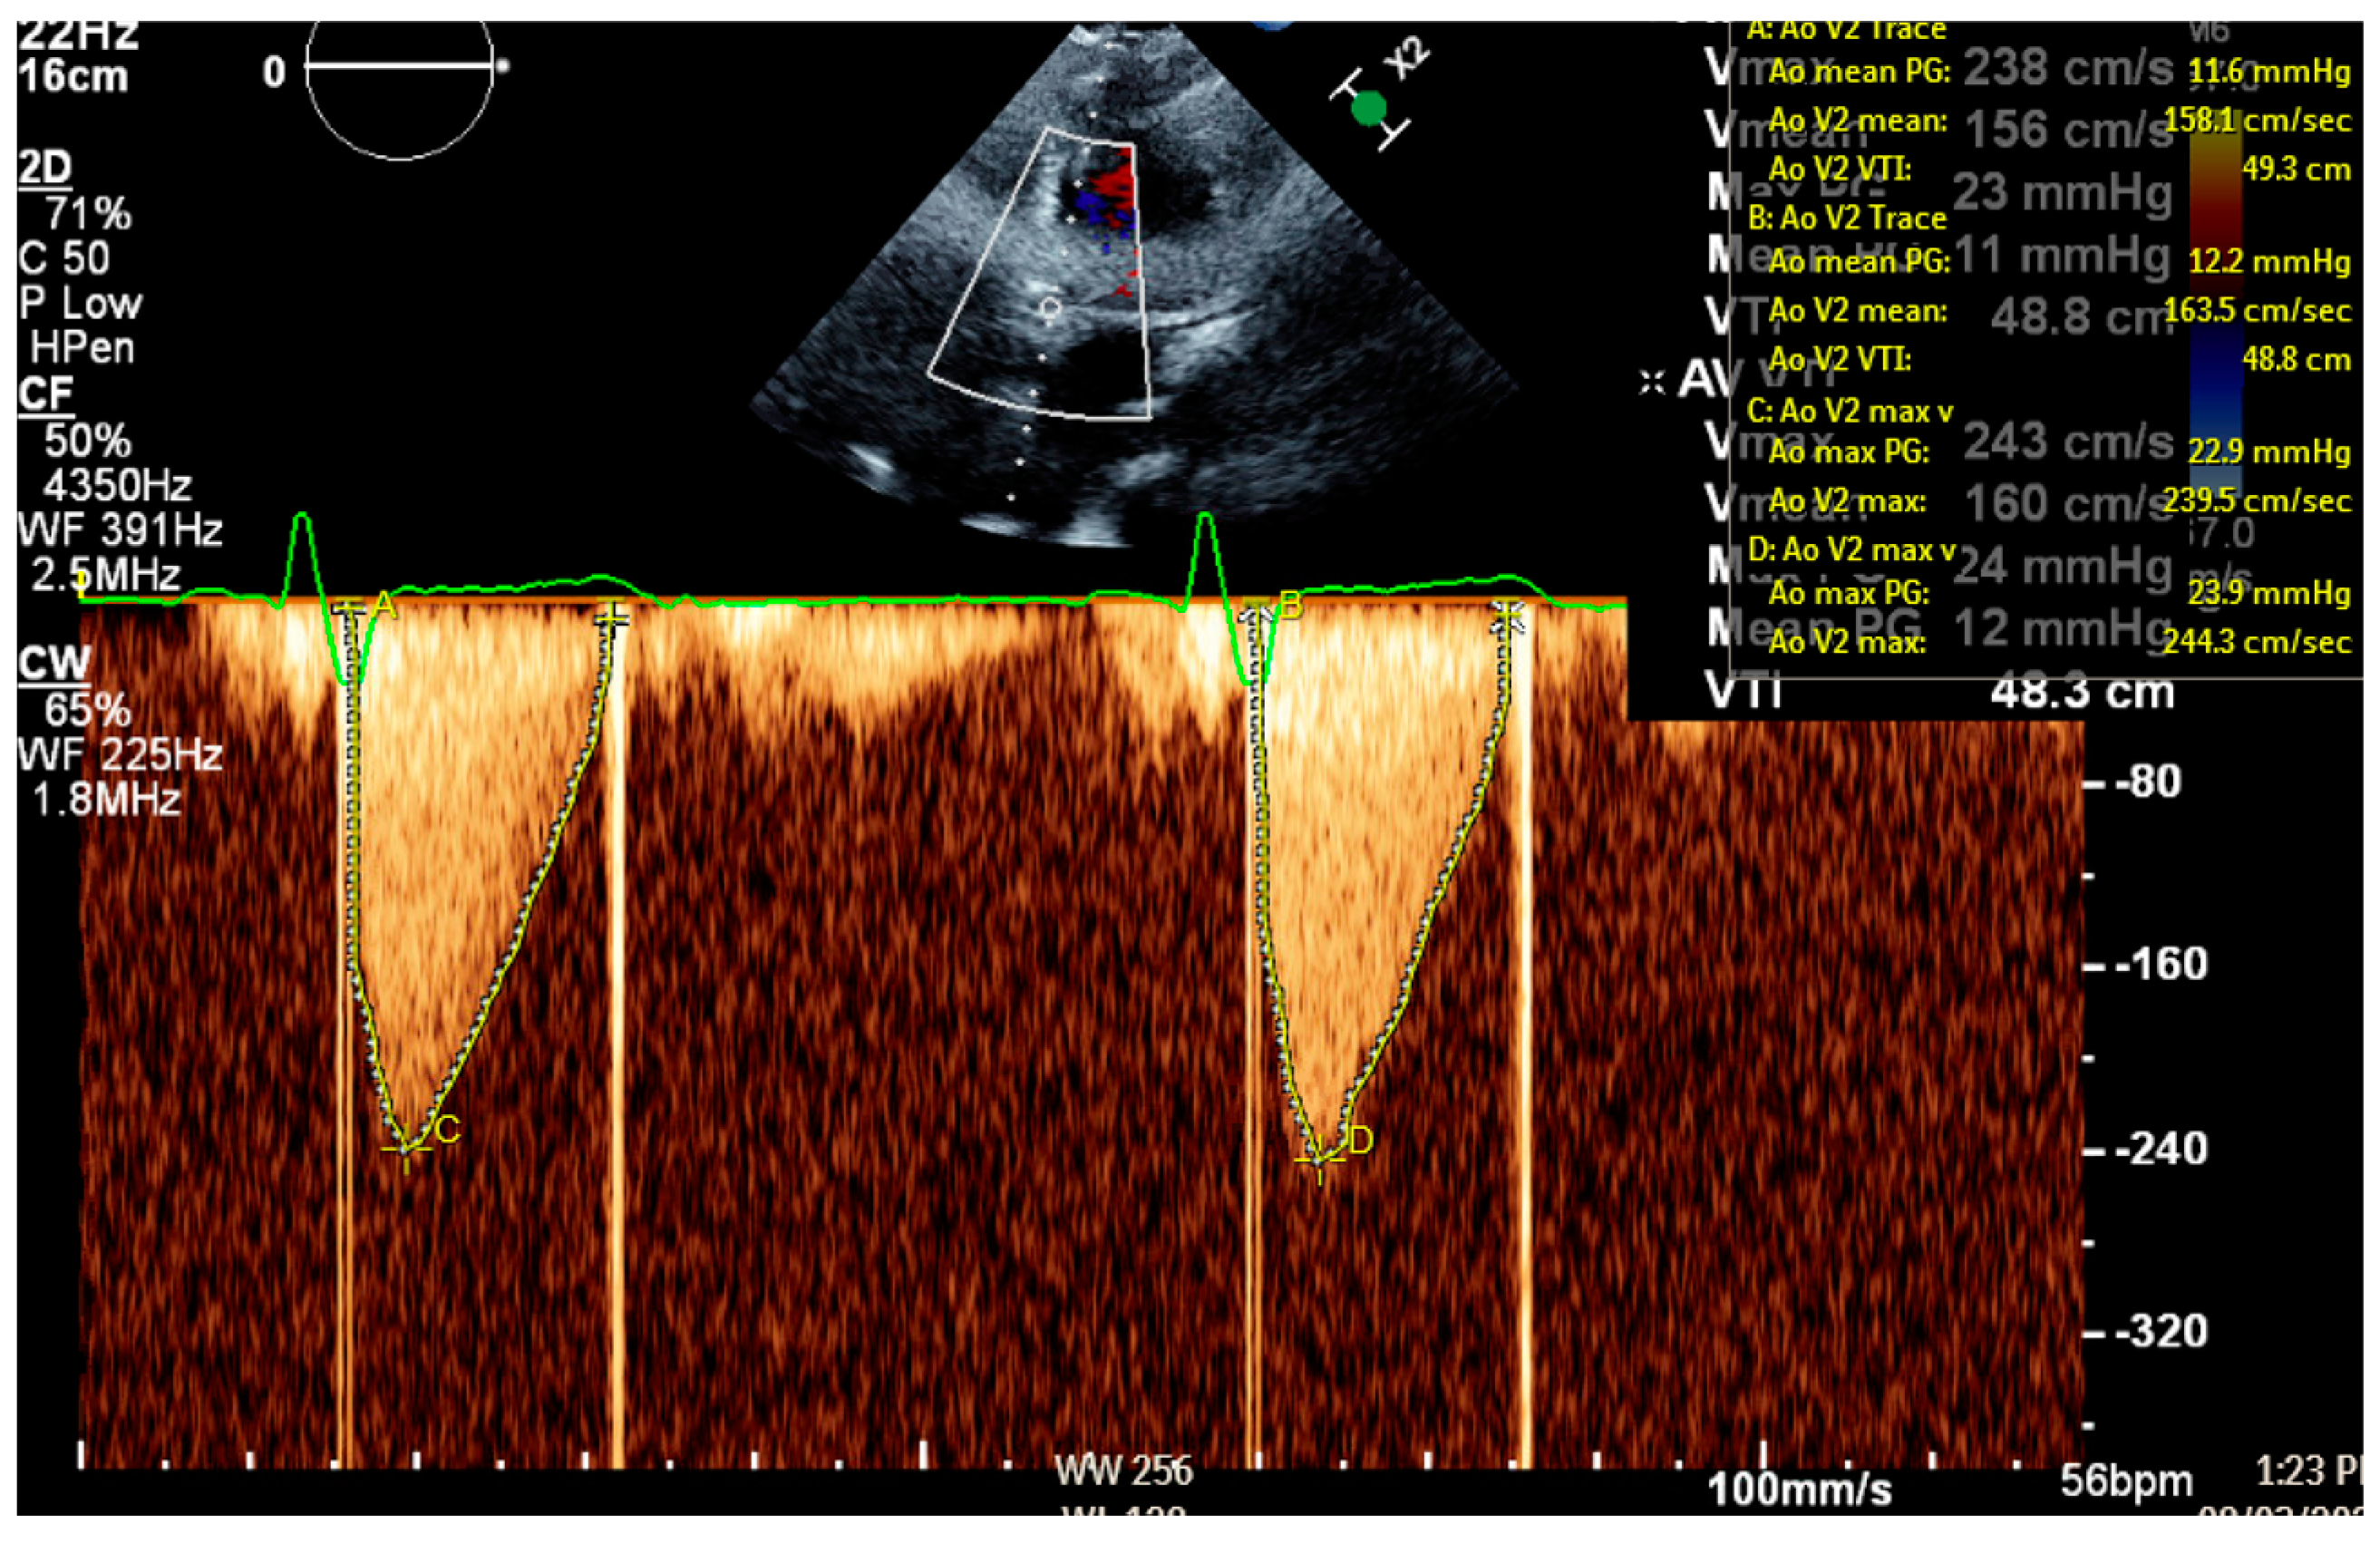

2. Patient Case